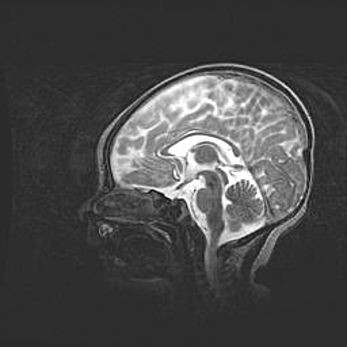

Мальформация Денди-Уокера. Киста задней черепной ямки.

Агенезия мозолистого тела.

Возраст: 2,5 месяца

Вес: 2420 г

Пол: женский

Окружность головы: 37 см

Срок гестации: 32 недели

Мальформация Денди—Уокера — редкий вид патологии ЦНС, представляющий собой врожденный порок развития каудального отдела ствола и червя мозжечка, ведущий к неполному раскрытию срединной (Мажанди) и латеральных (Лушка) апертур IV желудочка мозга. Для этогно синдрома характерна триада симптомов: гипотрофия червя мозжечка и/или полушарий мозжечка, кисты задней черепной ямки, гидроцефалия различной степени. В 70% случаев порок сочетается и с другими аномалиями головного мозга, в частности с агенезией мозолистого тела.